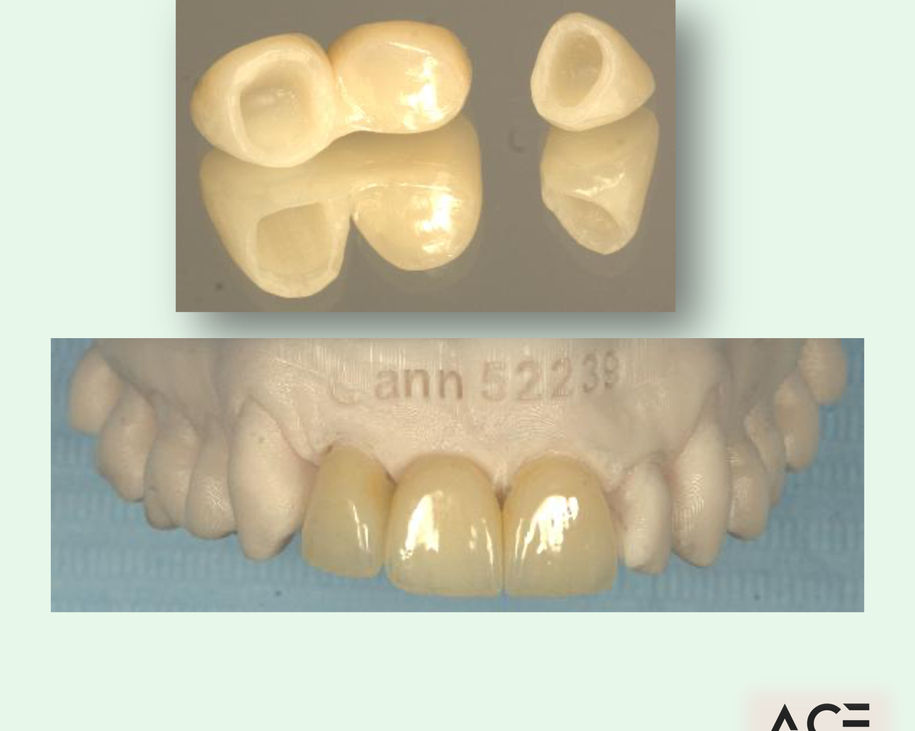

Alumni Outcomes showcasing below snippets of cases submitted as part diploma submissions

Dentists transitioning from routine dentistry into advanced restorative cases

Predictable clinical outcomes through structured protocols